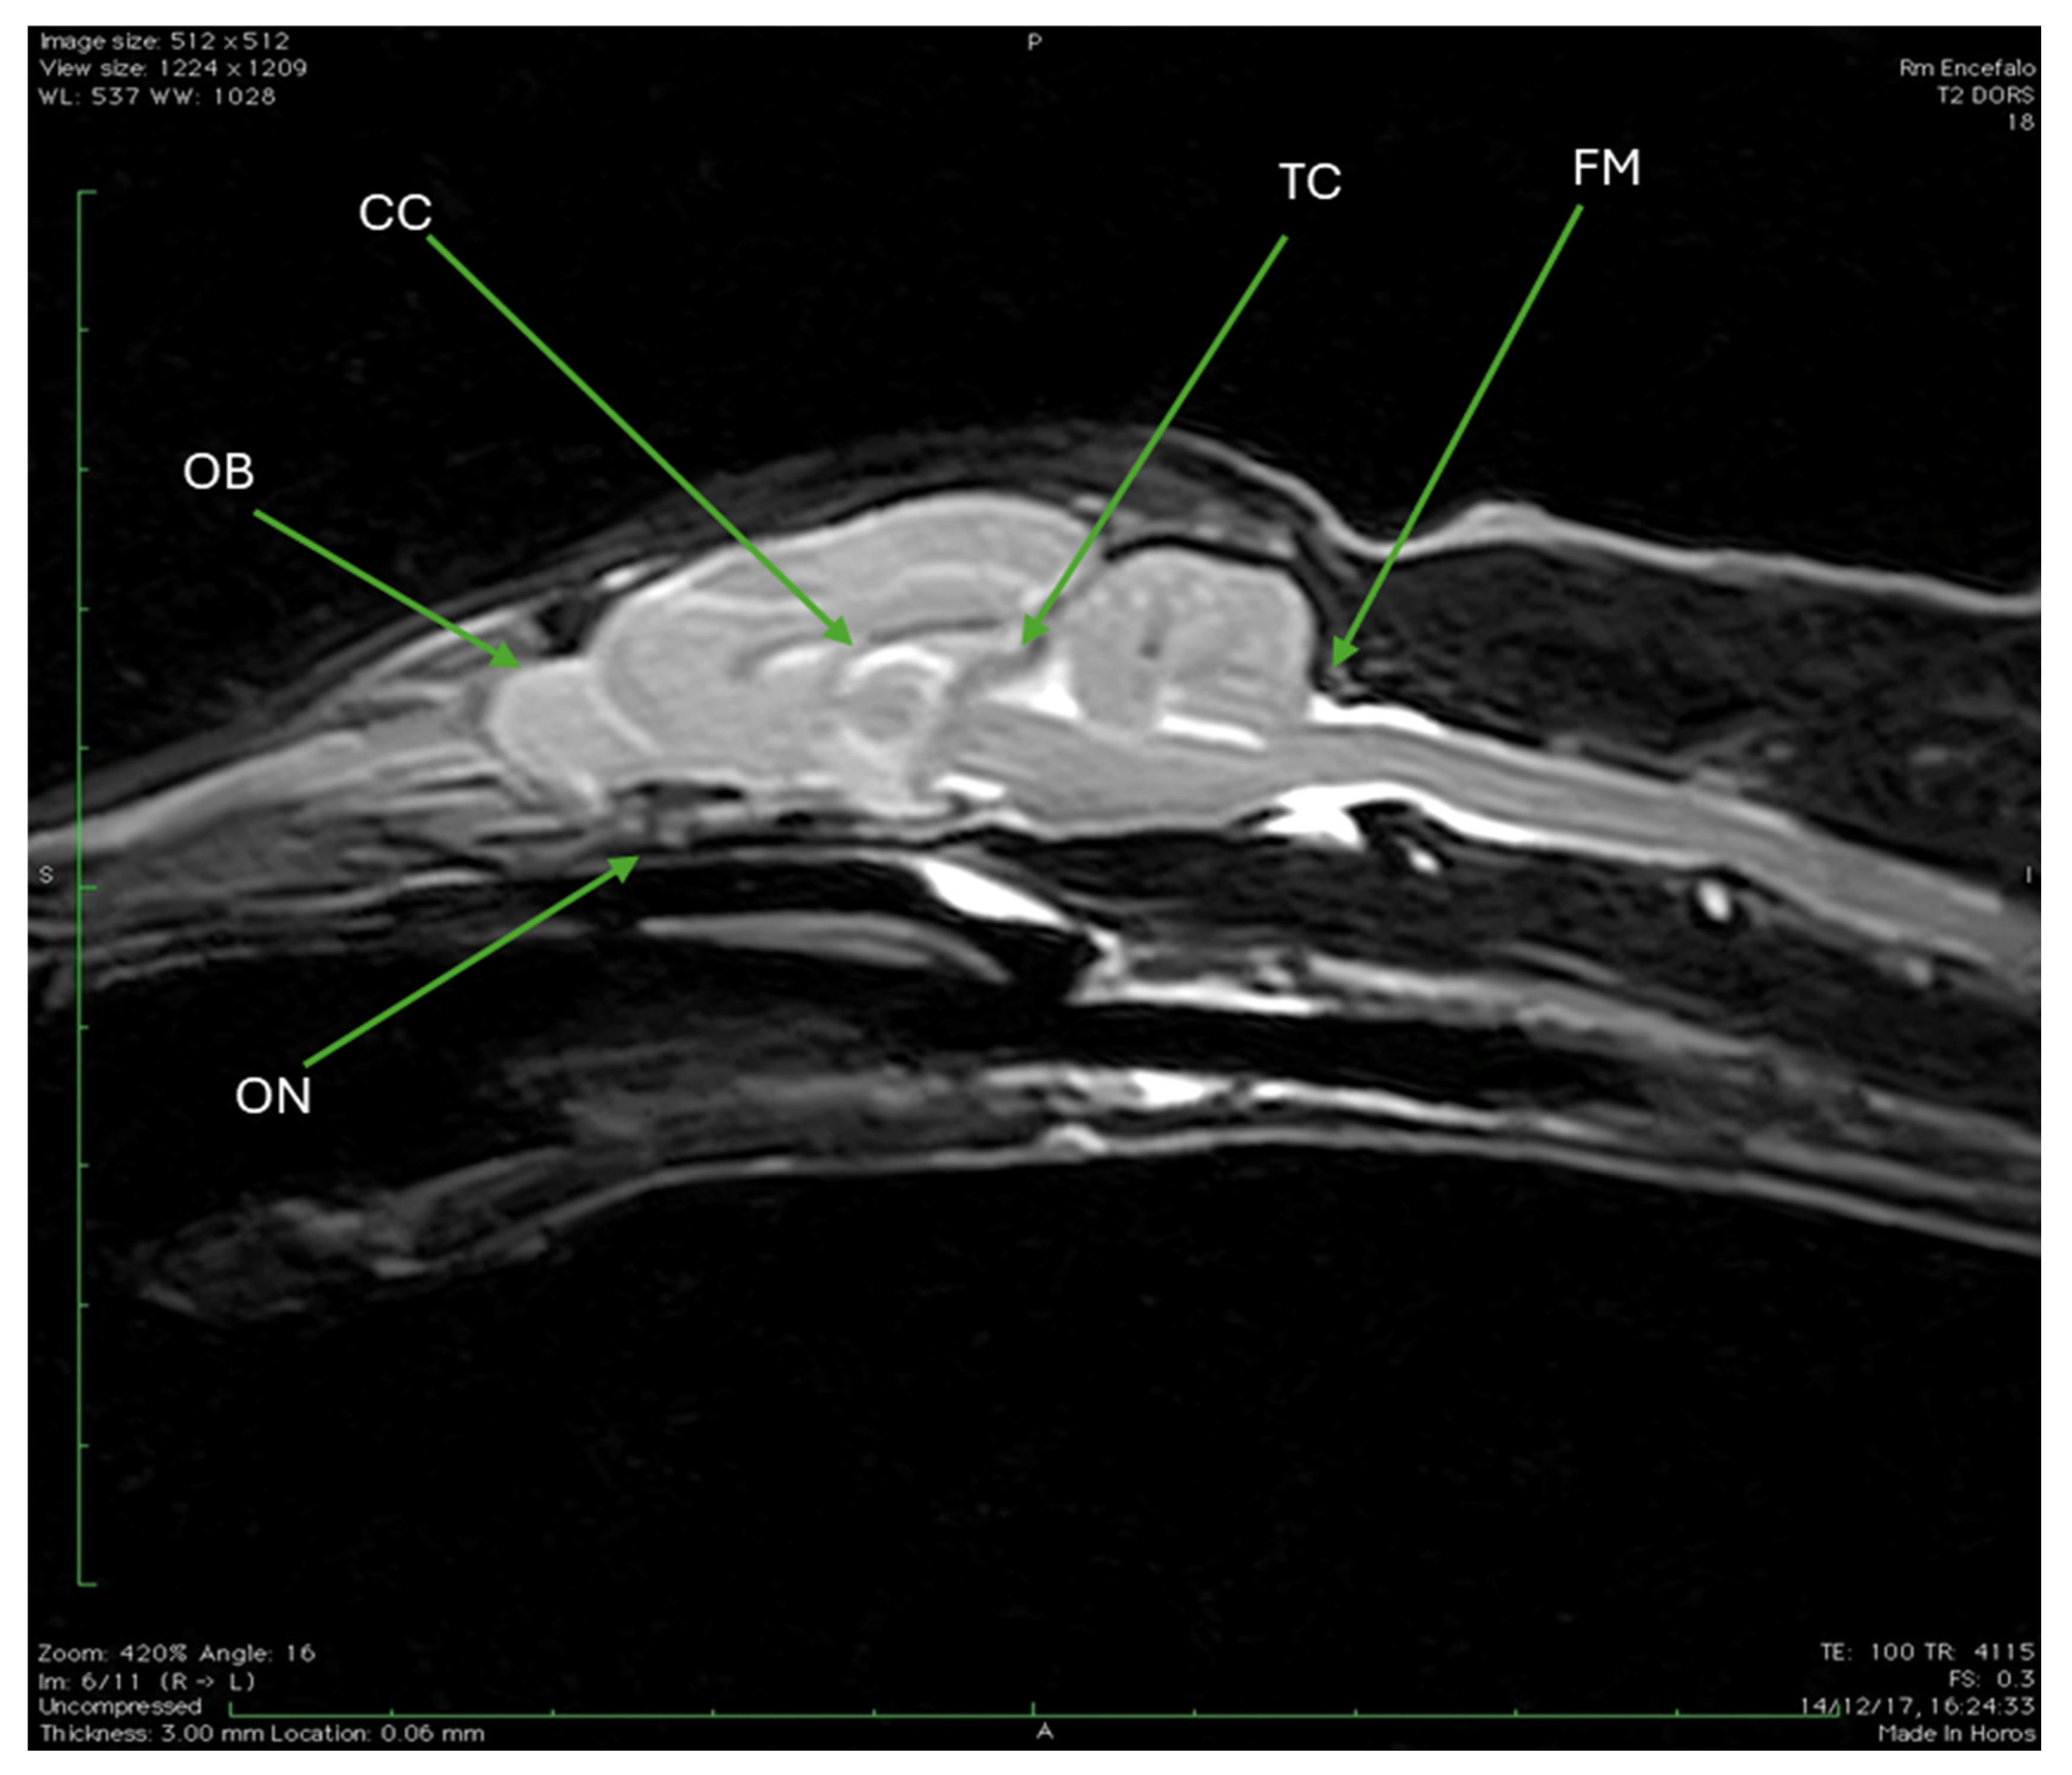

| OB | Olfactory bulb |

| ON | Optic nerve |

| TC | Tentorium cerebelli |

| FM | Foramen magnum |

4. Discussion